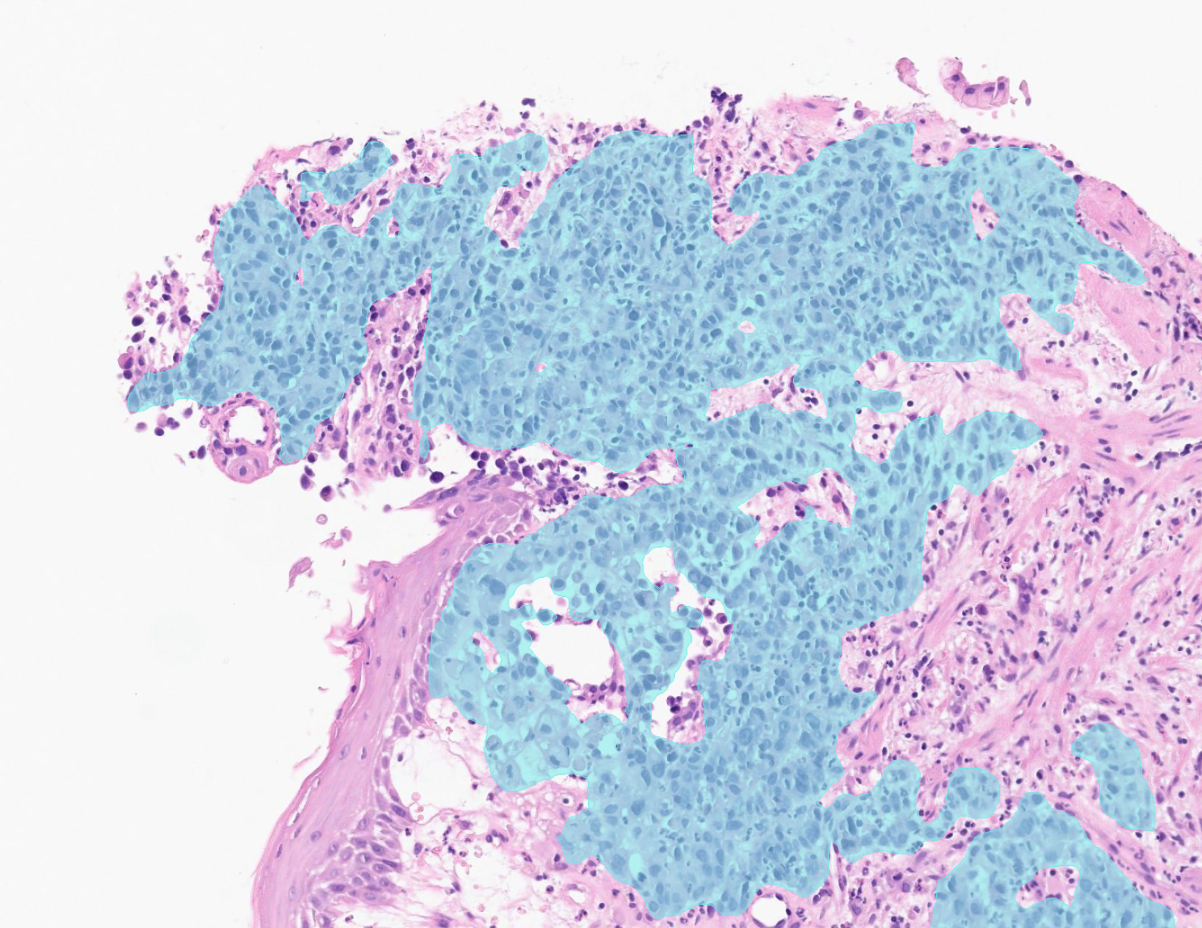

Aiforia® Gastric Suite uses AI to analyze digitized whole slide images to address these challenges. By highlighting suspicious areas directly on the slide, it enables efficient review while ensuring the pathologist remains in full control of interpretation and reporting.